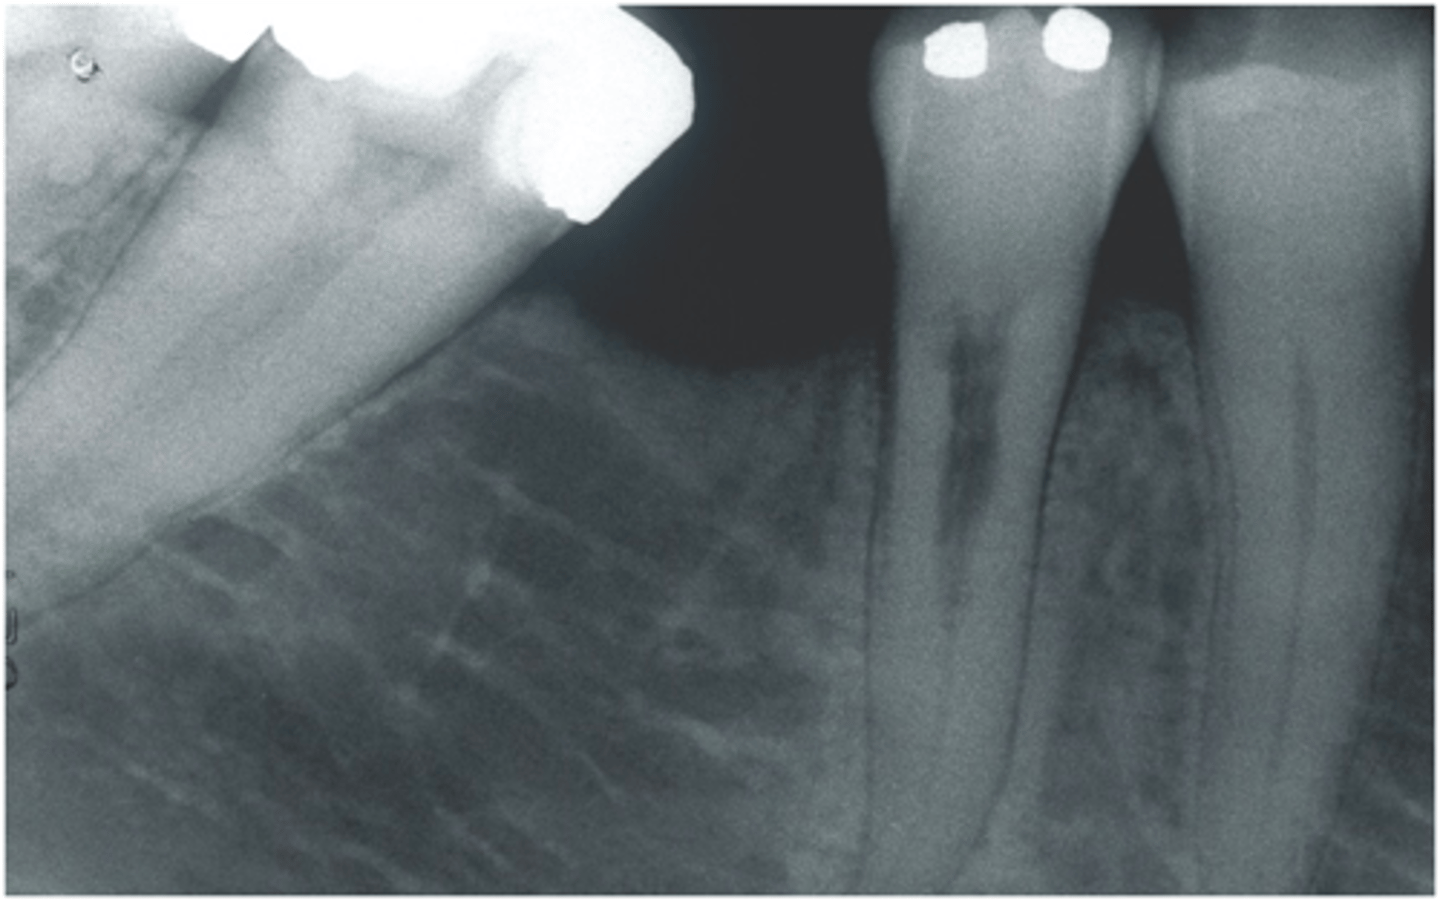

Check if missed MB2

RCT 10 years ago thru bridge

Sinus tract 3 years ago...apicoectomy done

Sinus tract returned.

What do we do?